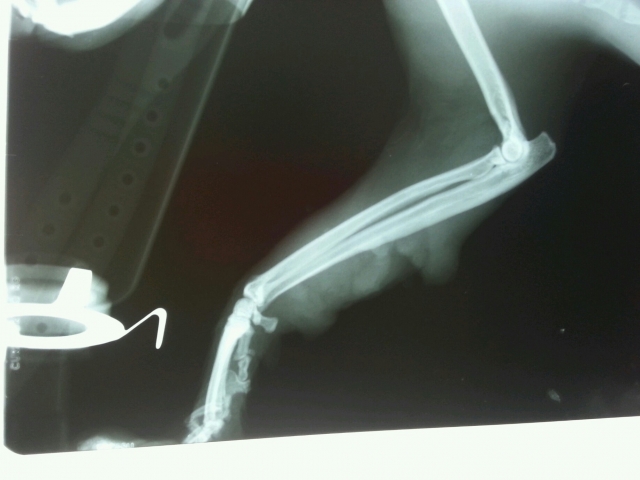

회복기 중 사진과 파열된 상처 엑스레이 사진 올립니다.

오른쪽 앞발 뒤 백원 동전크기 봉합,

왼쪽 앞발 뒤 백원 동전 세개 크기 봉합.